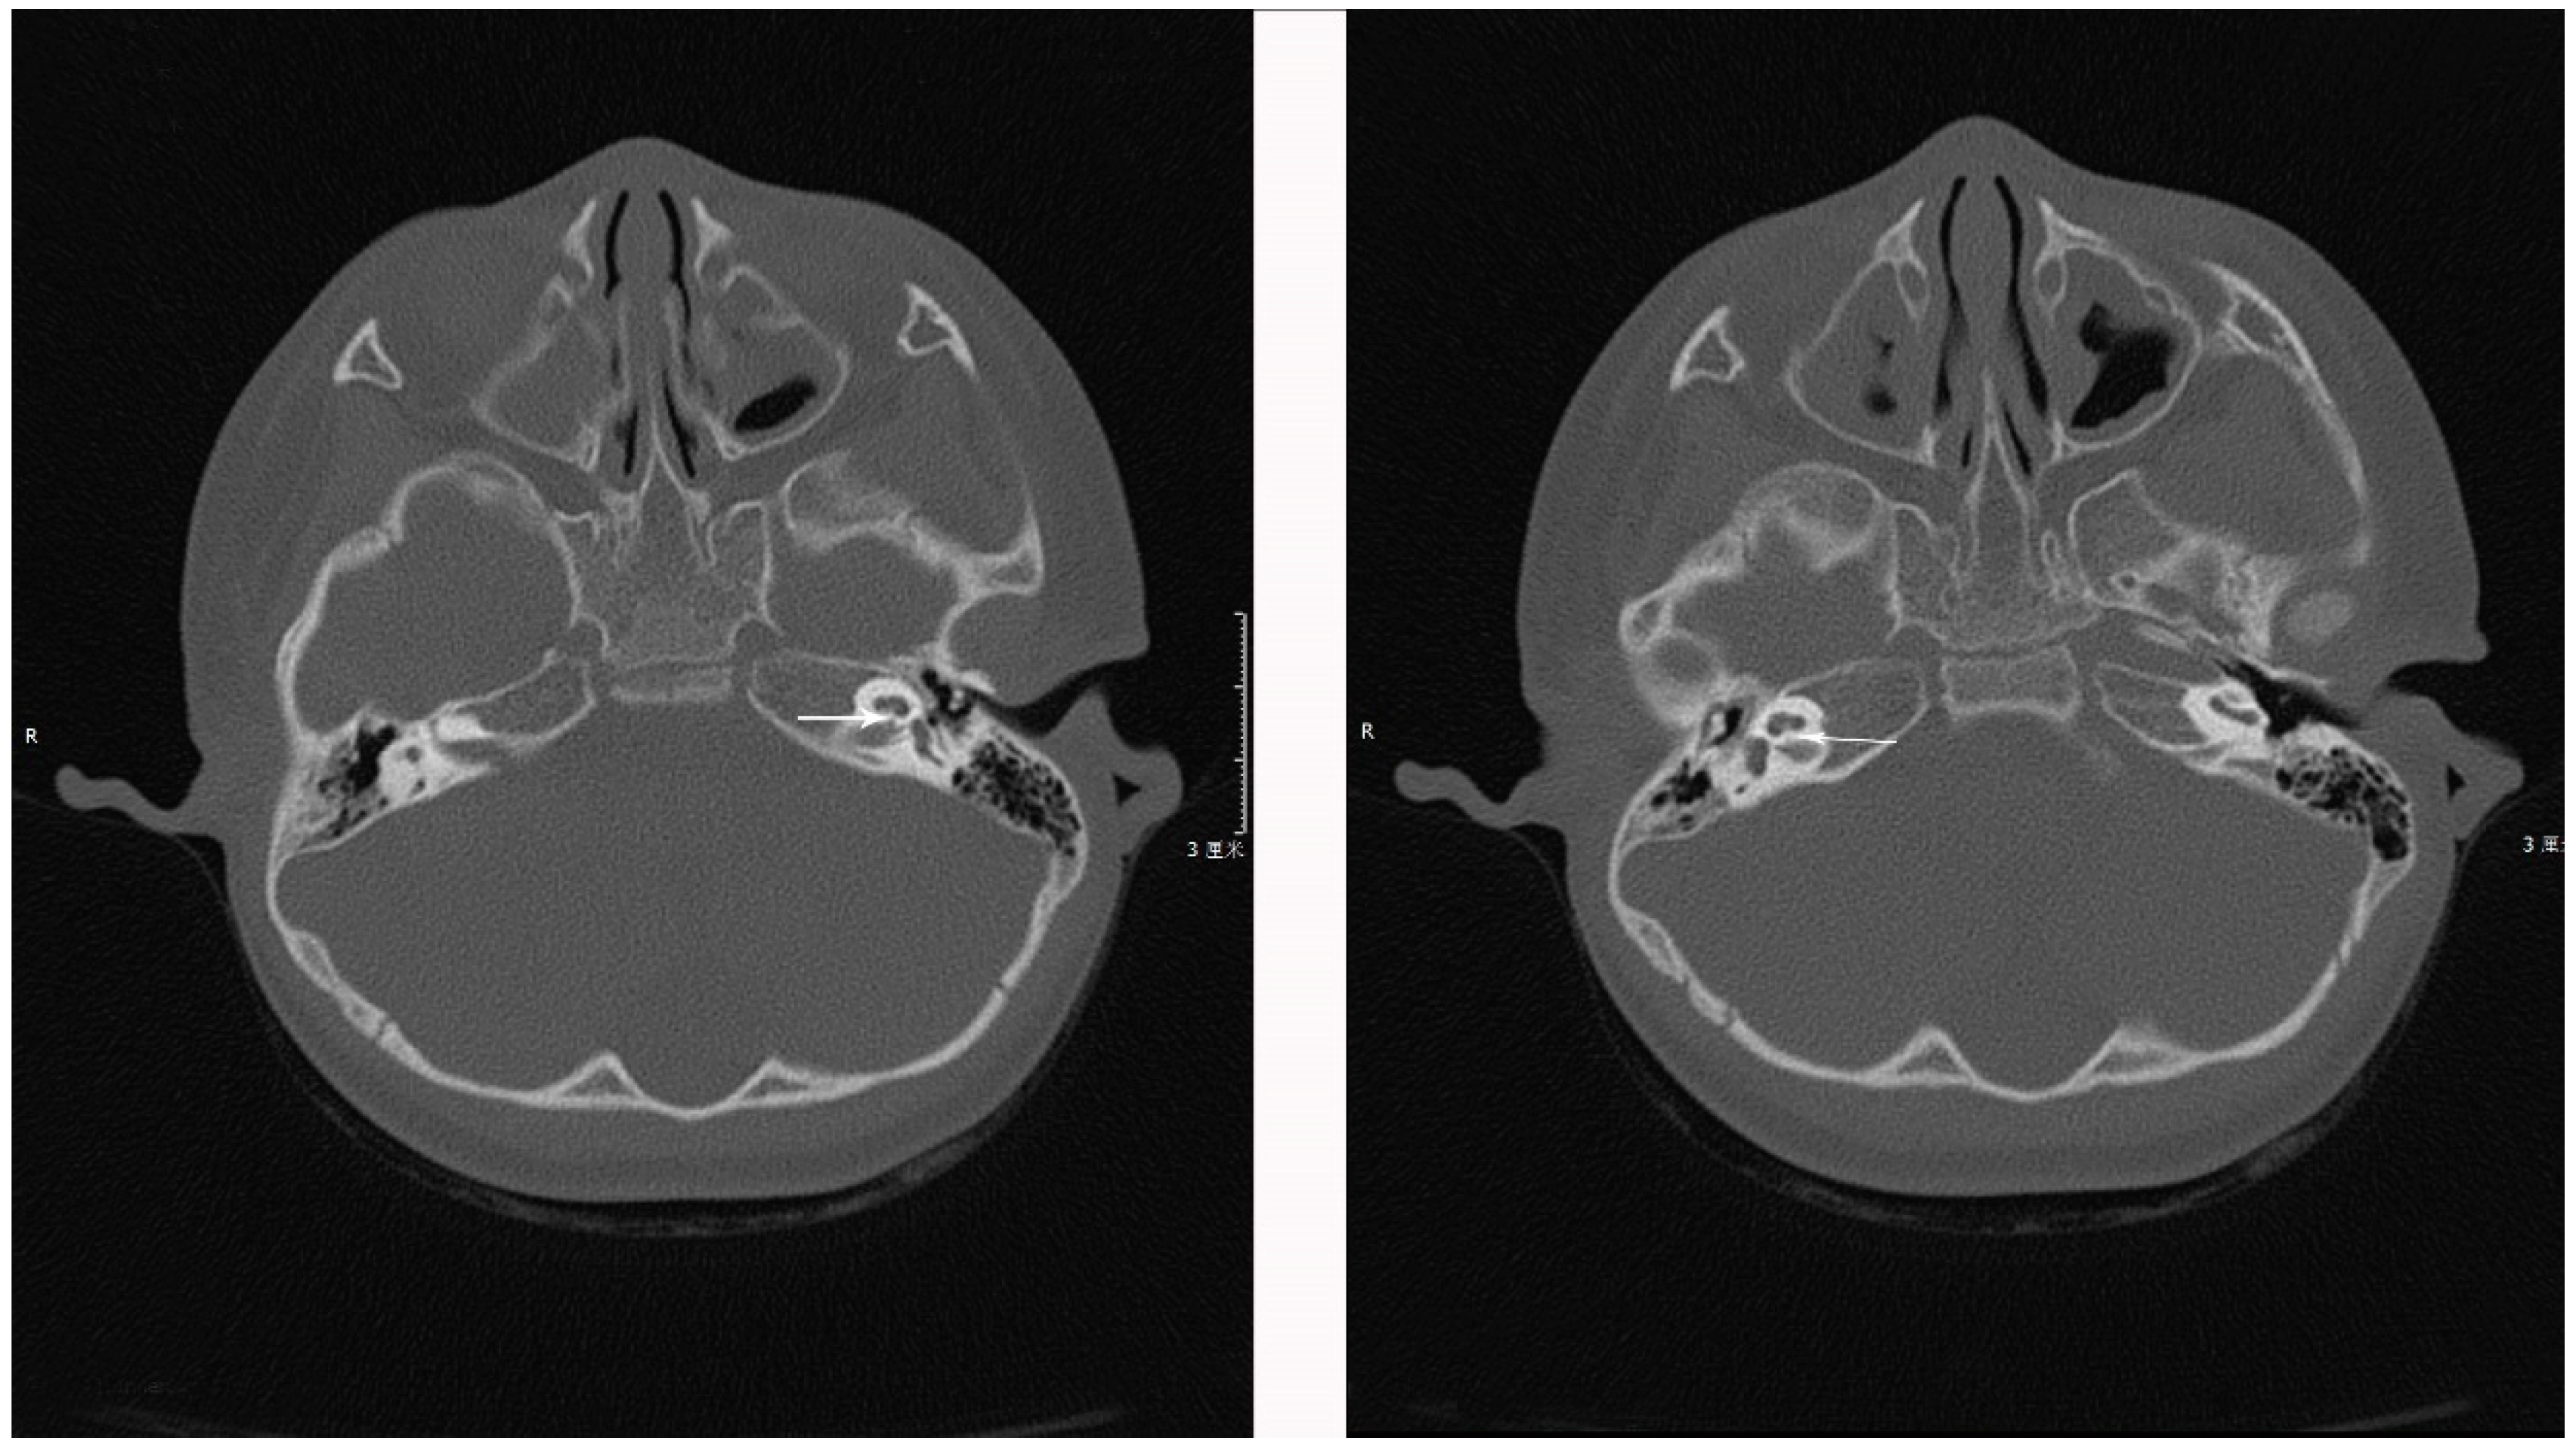

1.1. Case 1

1.2. Case 2